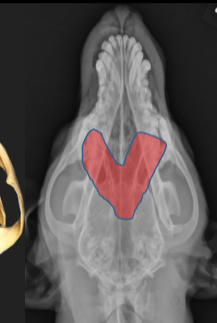

ID Radiographic View

Frontal Sinus View

ID

Frontal Sinus

Ethmoid Turbinates

Maxillary Turbinates

Nasopharynx

Maxillary Recess